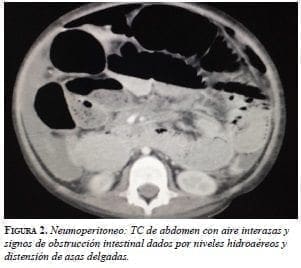

Presentó un cuadro clínico de dolor abdominal, obstrucción intestinal y ascitis de un mes evolución; además, síndrome de respuesta inflamatoria sistémica que produjo taquicardia y fiebre. Se requirió su hospitalización y la práctica de una laparotomía de urgencia. En la ecografía abdominal total se encontró líquido libre en la cavidad abdominal y, la tomografía computadorizada de abdomen contrastada con medio hidrosoluble, un neumoperitoneo masivo (figura 2).

Para el diagnóstico imaginológico, se puede emplear la ecografía abdominal total, la cual permite detectar líquido libre con tabiques finos y linfadenopatías con centro hipoecogénico, que corresponde a necrosis de caseificación. En la tomografía computadorizada de abdomen se aprecia engrosamiento de las asas, especialmente el íleon y la válvula ileocecal, con nódulos en el mesenterio, líquido libre, signos de obstrucción intestinal y perforación 17-19.

En la ecografía de este paciente se encontró líquido libre, escaso pero sin tabiques y no se evidenciaron adenomegalias, mientras que en la tomografía se observaron signos de obstrucción intestinal con perforación 20, 21. La colonoscopia se puede emplear con el fin de detectar lesiones en la válvula ileocecal y en el íleon distal; sin embargo, los hallazgos pueden ser similares a los de la enfermedad de Crohn, como lo reportan Wu, et al. En la esofagogastroduodenoscopia no se demostraron ulceraciones sugestivas de tuberculosis 22- 24.